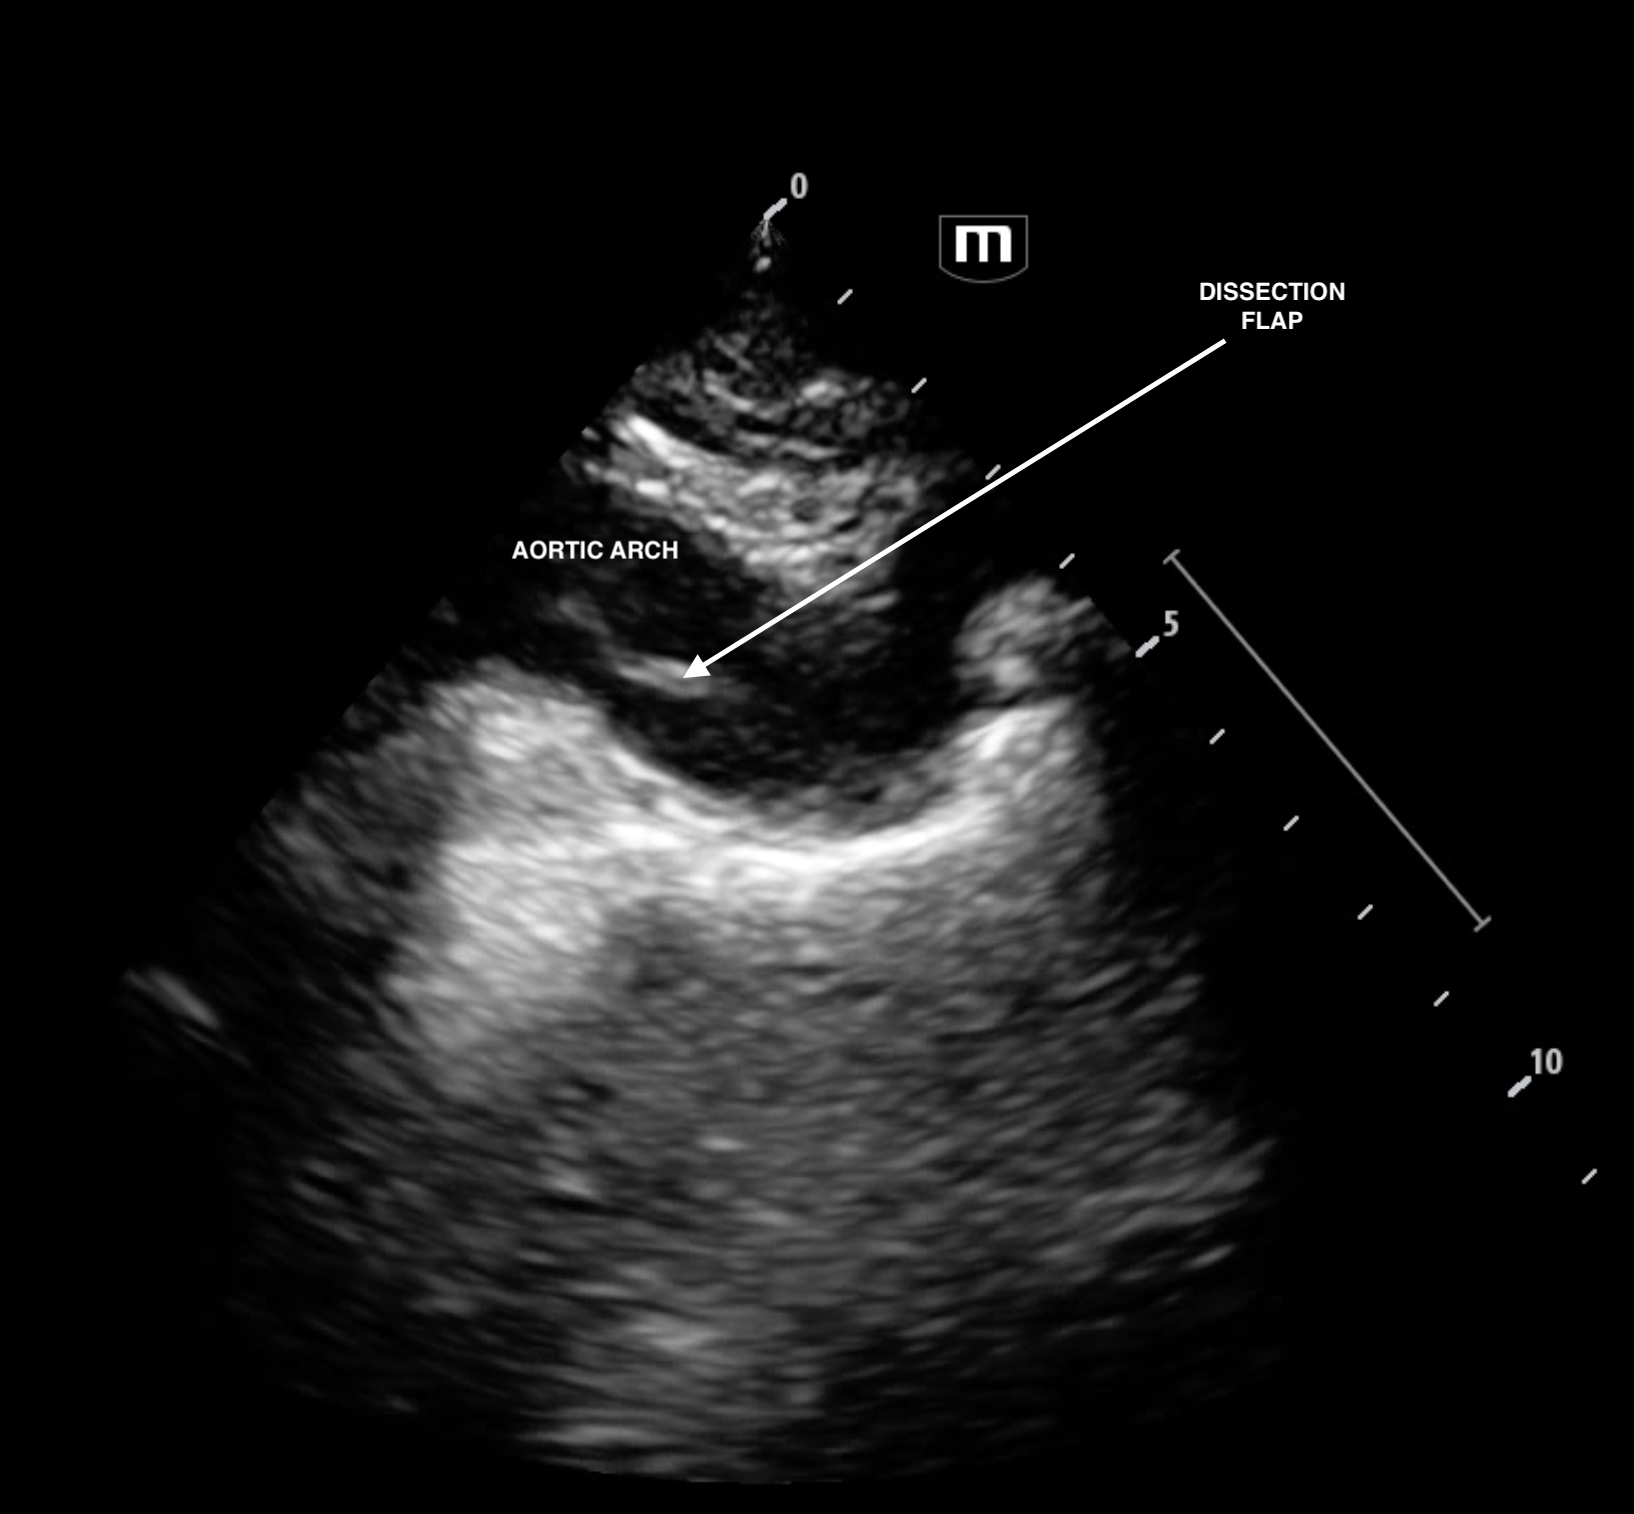

The dissection flap is seen more easily in the suprasternal view. The patient was fortunately NOT thrombolysed because of the bedside echo and went from CT to theatre in just under 2 hours and was successfully dc from hospital to rehab.

suprasternal view

Still of the suprasternal cine loop from above with arrow pointing to dissection flap.